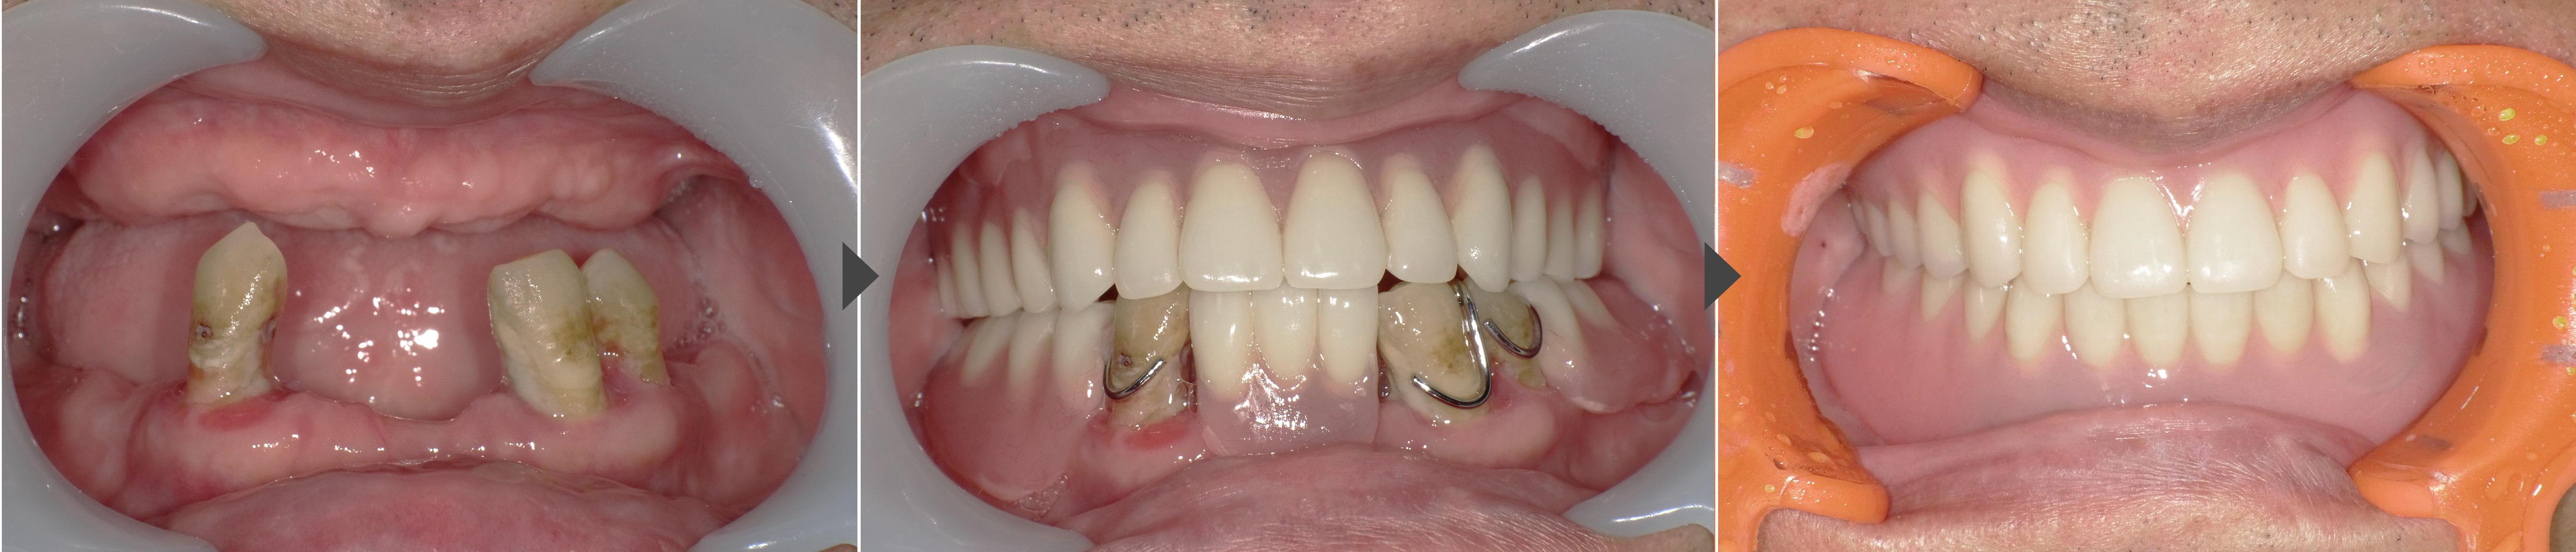

噛み合わせ(顎の位置)を安定させるため、まず治療用の仮入れ歯を作りました。この仮入れ歯を使って咬み合わせの高さや口元のバランスを確認し、手術の際もこの顎位を維持できるよう準備しました。

そのうえで、手術当日に残っている歯を抜歯し、同じ日にインプラントを2本埋め込み、ロケーター(金具)を装着して入れ歯を固定する「即時荷重」を行いました。

③ ロケーター装着・即時荷重

手術当日にロケーターアバットメントを取り付け、治療用義歯を内側から調整。その場でインプラントに適合させることで、当日からしっかり噛める状態を確保しました。

3か月ほど経過を観察し、インプラントが骨と安定的に結合したことを確認。その後、見た目・咬み合わせ・発音などをさらに整えた最終のロケーターデンチャーを作りました。

今回の症例では、治療用義歯であごの位置を安定させたうえで、抜歯と同時にインプラントを埋め込み、ロケーターを即時装着しました。

手術当日から入れ歯を使えるようにすることで、見た目や咬み合わせを保ちながら、早期に快適な咀嚼機能を回復できました。「入れ歯が合わない」「動いて痛い」「インプラント固定式までは望まない」という方に、ロケーターデンチャーは現実的で安心できる選択肢です。